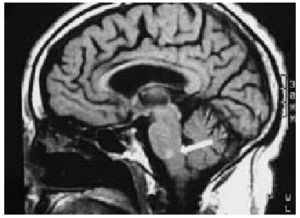

Varón de 71 años de edad, que fue ingresado por presentar un cuadro de dolor precordial de características coronarias en el ECG, presentaba una corriente de lesión subepicárdica inferior y lateral baja y escaso crecimiento de ondas R en las precordiales derechas por probable necrosis anteroseptal antigua. Se procede a la realización de una fibrinolisis con tenecteplasa, manteniendo perfusión de heparina sódica, antiagregación con ácido acetilsalicílico y nitritos. A las 4 h de la fibrinolisis aparece diplopía y afección del VI par craneal izquierdo; se realizó una tomografía computarizada craneal que mostró una dudosa imagen hiperintensa localizada en troncoencéfalo de 1 ml. Con objeto de completar el estudio se realizó una resonancia magnética nuclear craneal (figs. 1 y 2), que mostró una lesión ovalada de 1 cm en la unión bulboprotuberancial izquierda hiperintensa (con centro más hipointenso, en relación con la evolución normal de los componentes de la hemoglobina). El diagnóstico fue de hematoma intraparenquimatoso en la unión bulbomedular izquierda. La evolución posterior fue satisfactoria, con restitución ad integrum a los 2 meses. El juicio clínico fue de hematoma de la unión bulboprotruberancial secundario a fibrinolisis.

Figura 2.